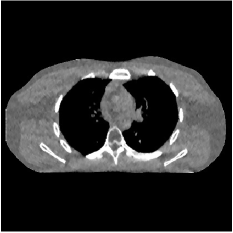

Fig. 2 shows representative reconstructions for FBP, PWLS-EP, PWLS-ST, and PWLS-MRST2. Compared to FBP and PWLS-EP, PWLS-MRST2 significantly improves image quality by reducing noise and preserving structural details. Furthermore, PWLS-MRST2 improves the quality of the central region and image edges compared to PWLS-ST.

| (a) FBP | (b) PWLS-EP | (c) PWLS-ST | (d) PWLS-MRST2 |